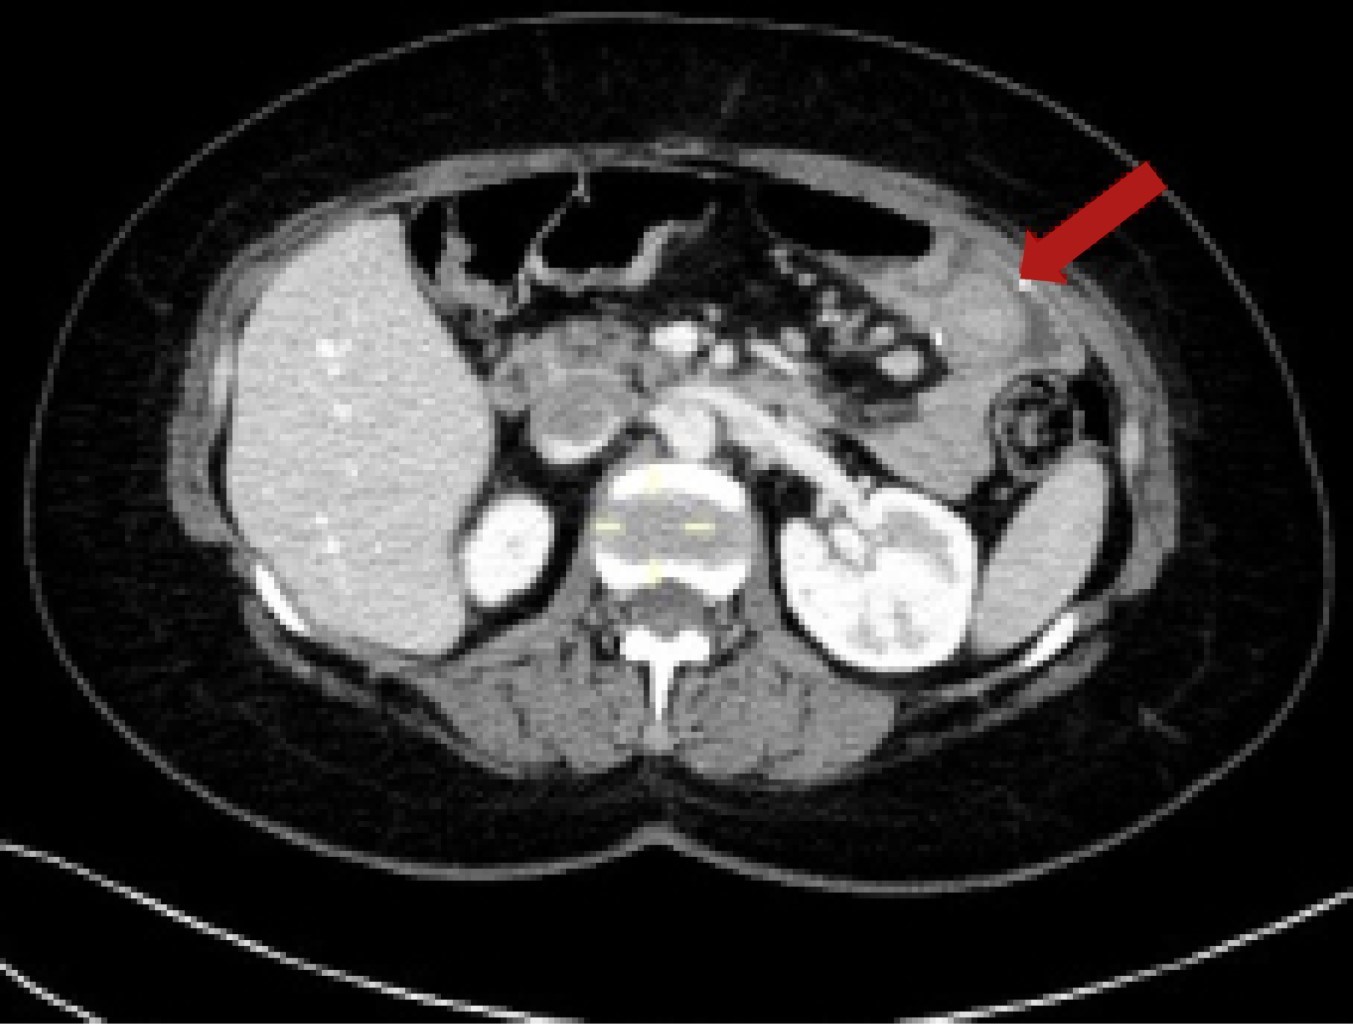

Chronic Gastrojejunal Fistula Plus Intestinal Intussusception As A